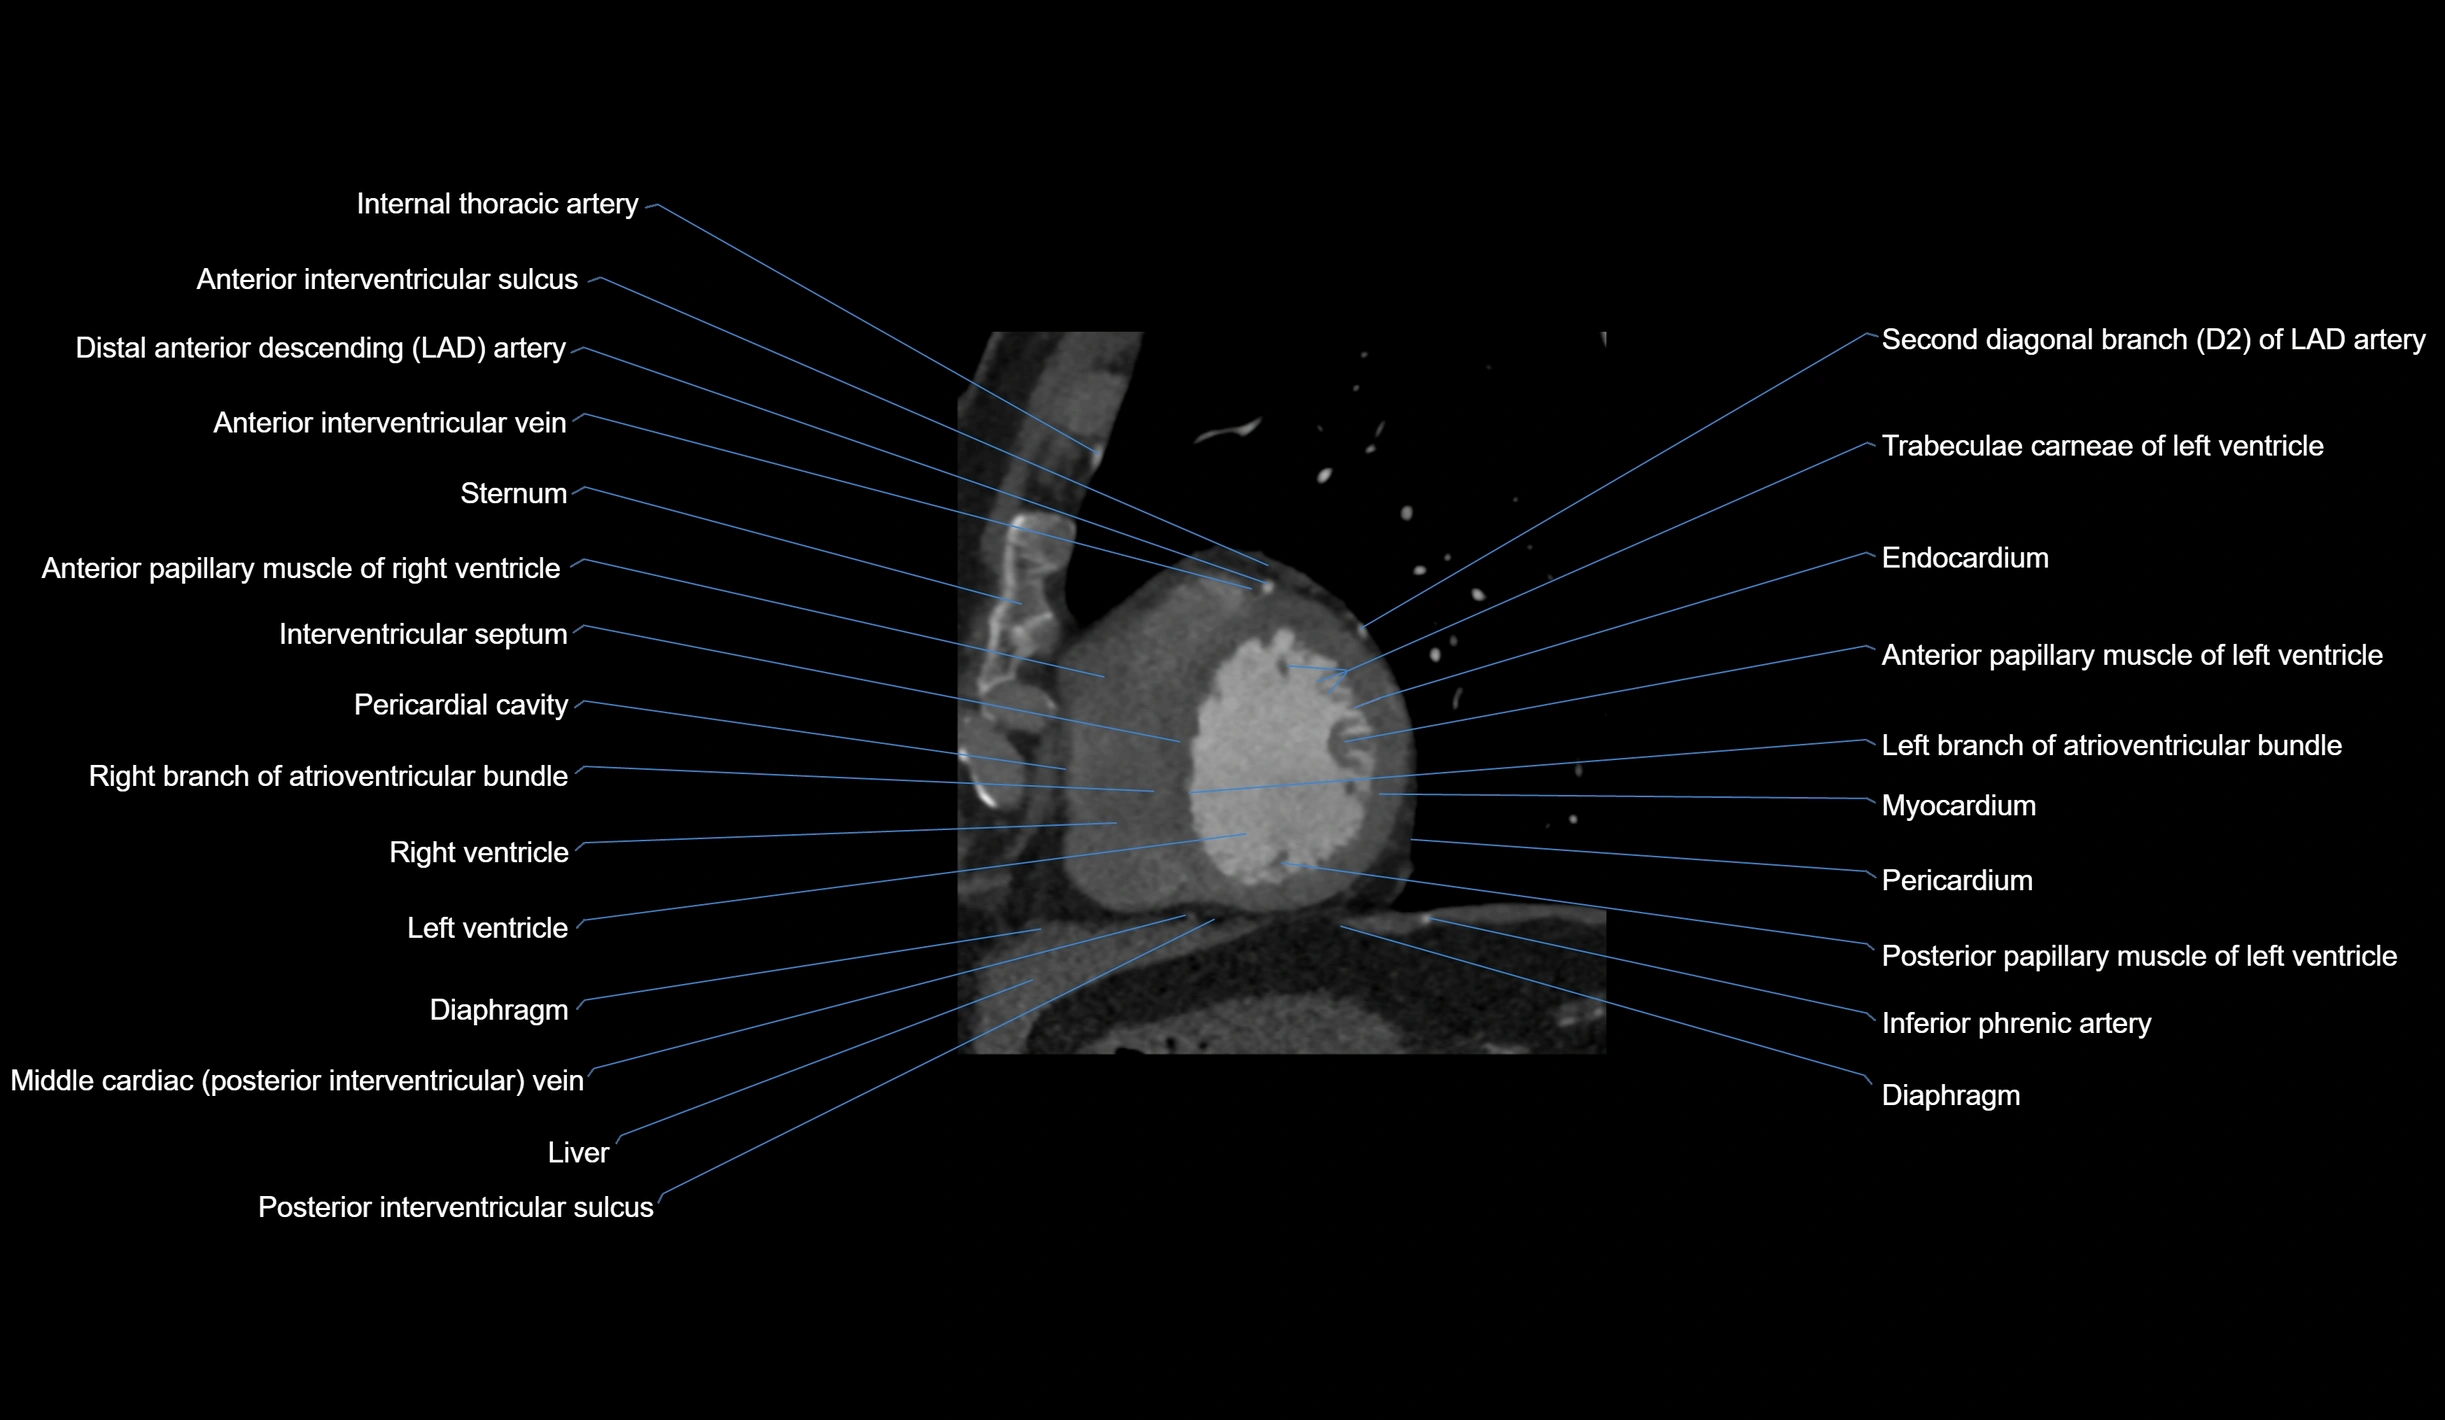

- Anterior interventricular sulcus

- Anterior papillary muscle

- Diaphragm

- Endocardium

- Interventricular Septum

- Left branch of atrioventricular bundle

- Myocardium

- Pericardial cavity

- Pericardium

- Right branch of atrioventricular bundle

- Right ventricle

- Second diagonal branch (D2) of LAD

- Sternum

- Trabeculae carneae